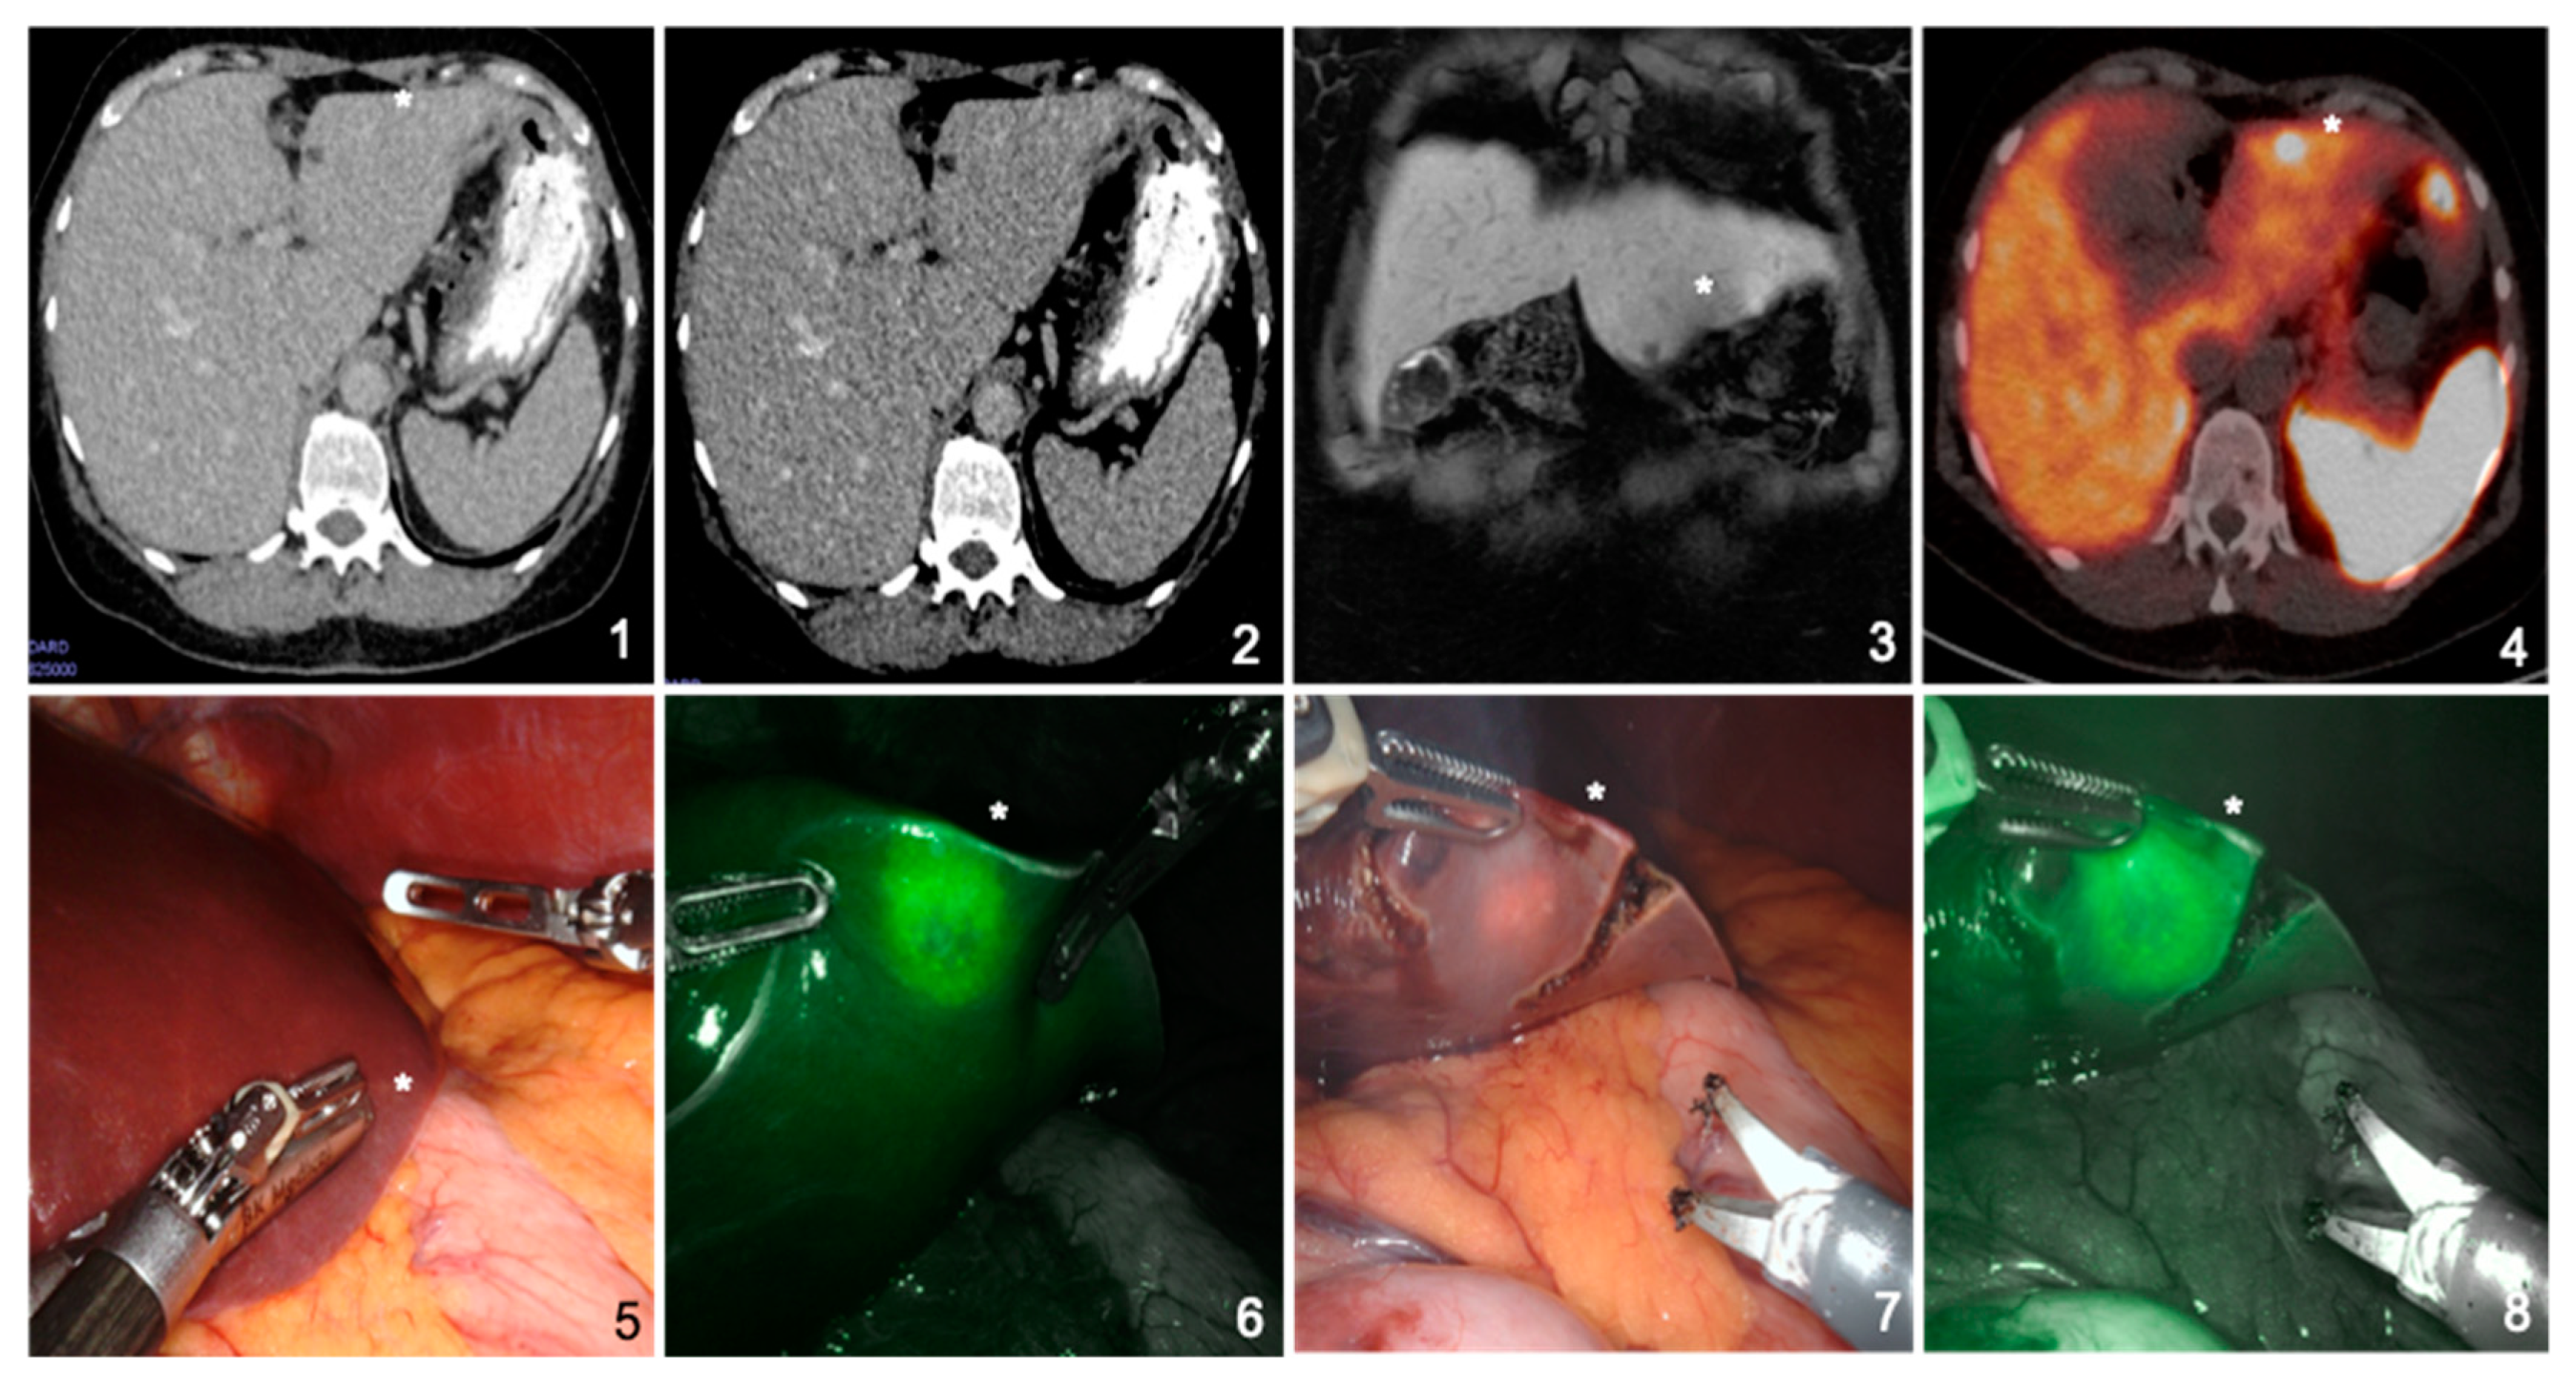

Usability of Indocyanine Green in Robot-Assisted Hepatic Surgery

Mehdorn, A.-S.; Beckmann, J.H.; Braun, F.; Becker, T.; Egberts, J.-H. Usability of Indocyanine Green in Robot-Assisted Hepatic Surgery. J. Clin. Med. 2021, 10, 456. https://doi.org/10.3390/jcm10030456